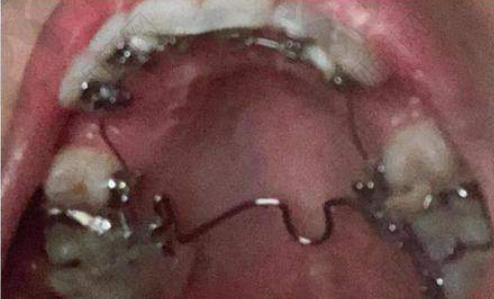

孔卫东医生舌侧隐形矫正实例

曾经有一位成年患者,牙齿排列不齐,存在重度的错颌畸形问题,对美观和咀嚼功能都造成了较大影响。患者尝试过多种矫正方法,但成效都不理想。后来找到了孔卫东医生,孔医生为他进行了详细的检查和评估,决定采用舌侧隐形矫正技术。在矫正过程中,孔医生根据患者牙齿的移动情况,及时调整矫正方案。经过一段时间的矫正,患者的牙齿逐渐变得整齐,面部美观度也得到了明显提升。患者对矫正成效非常满意,重拾了自信。